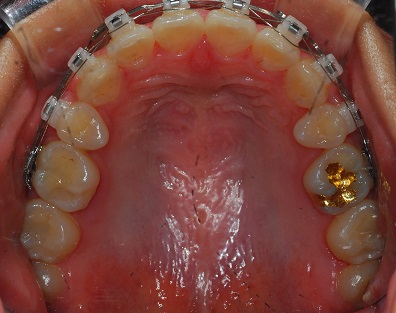

상악 사진